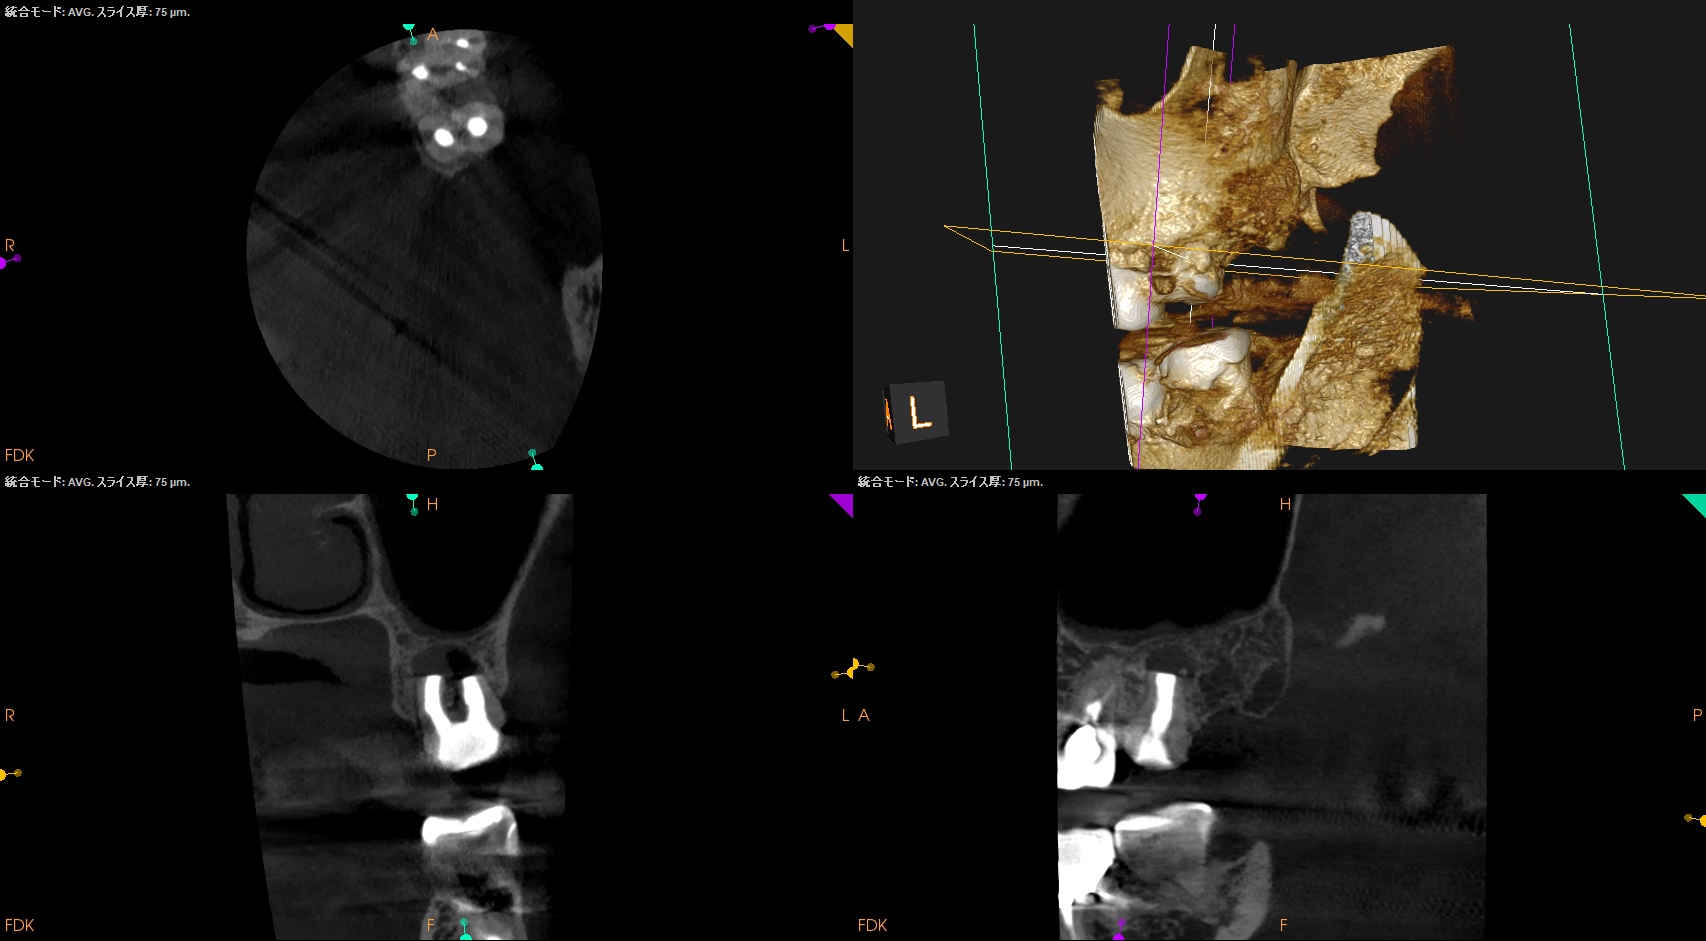

術後にPA, CBCTを撮影した。

この1ヶ月後に再診があり、歯牙をチェックした。

#15 Intentional Replantation 1M recall(2026.1.21)

動揺も生理的な範囲内だ。

ということで、プロビジョナルレストレーションの装着を依頼した。